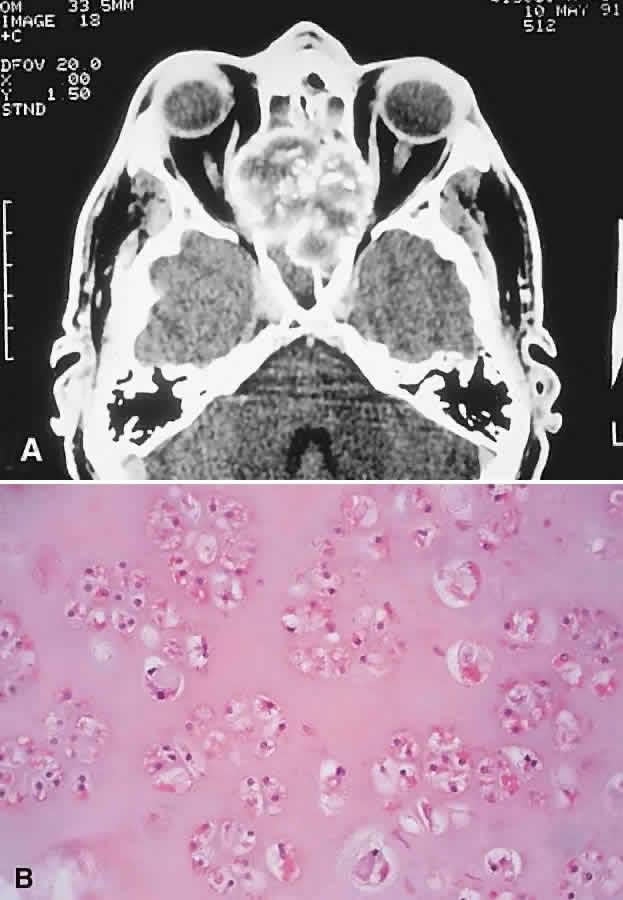

| The above clinical patterns correlate reasonably well with the following